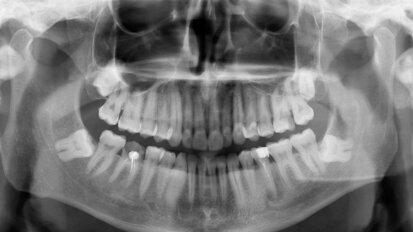

Treatment of severe oral pathology in pre-geriatric patients: A proposal for a clinical protocol for same-day dentistry

Modern restorative and prosthetic dentistry have undergone significant advances over the last five years. Innovations in dental materials have truly ...